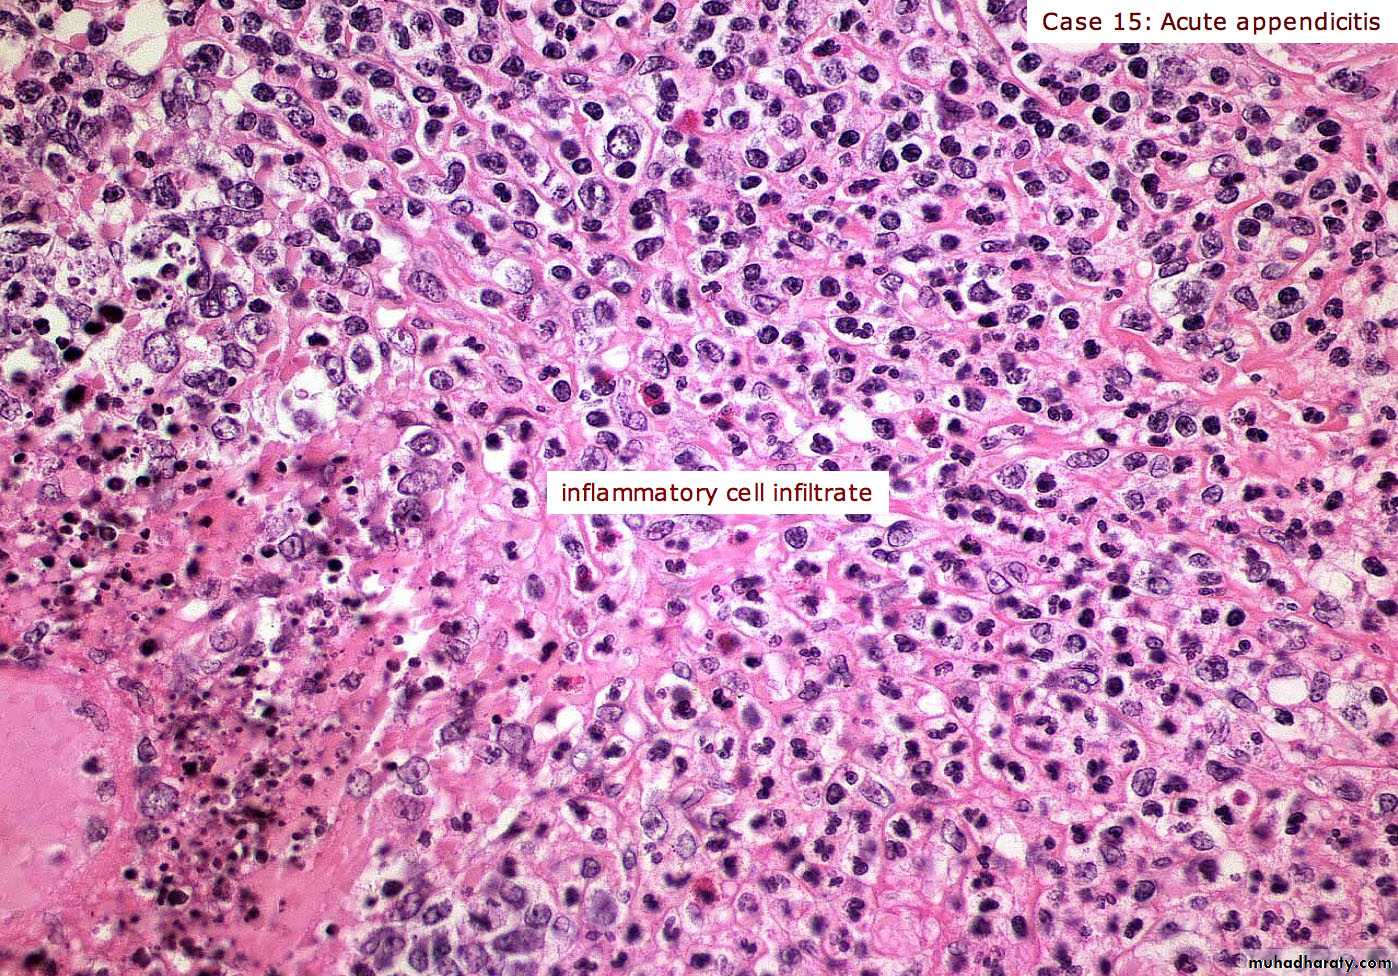

Acute & CHRONIC

Inflammation

Acute appendix